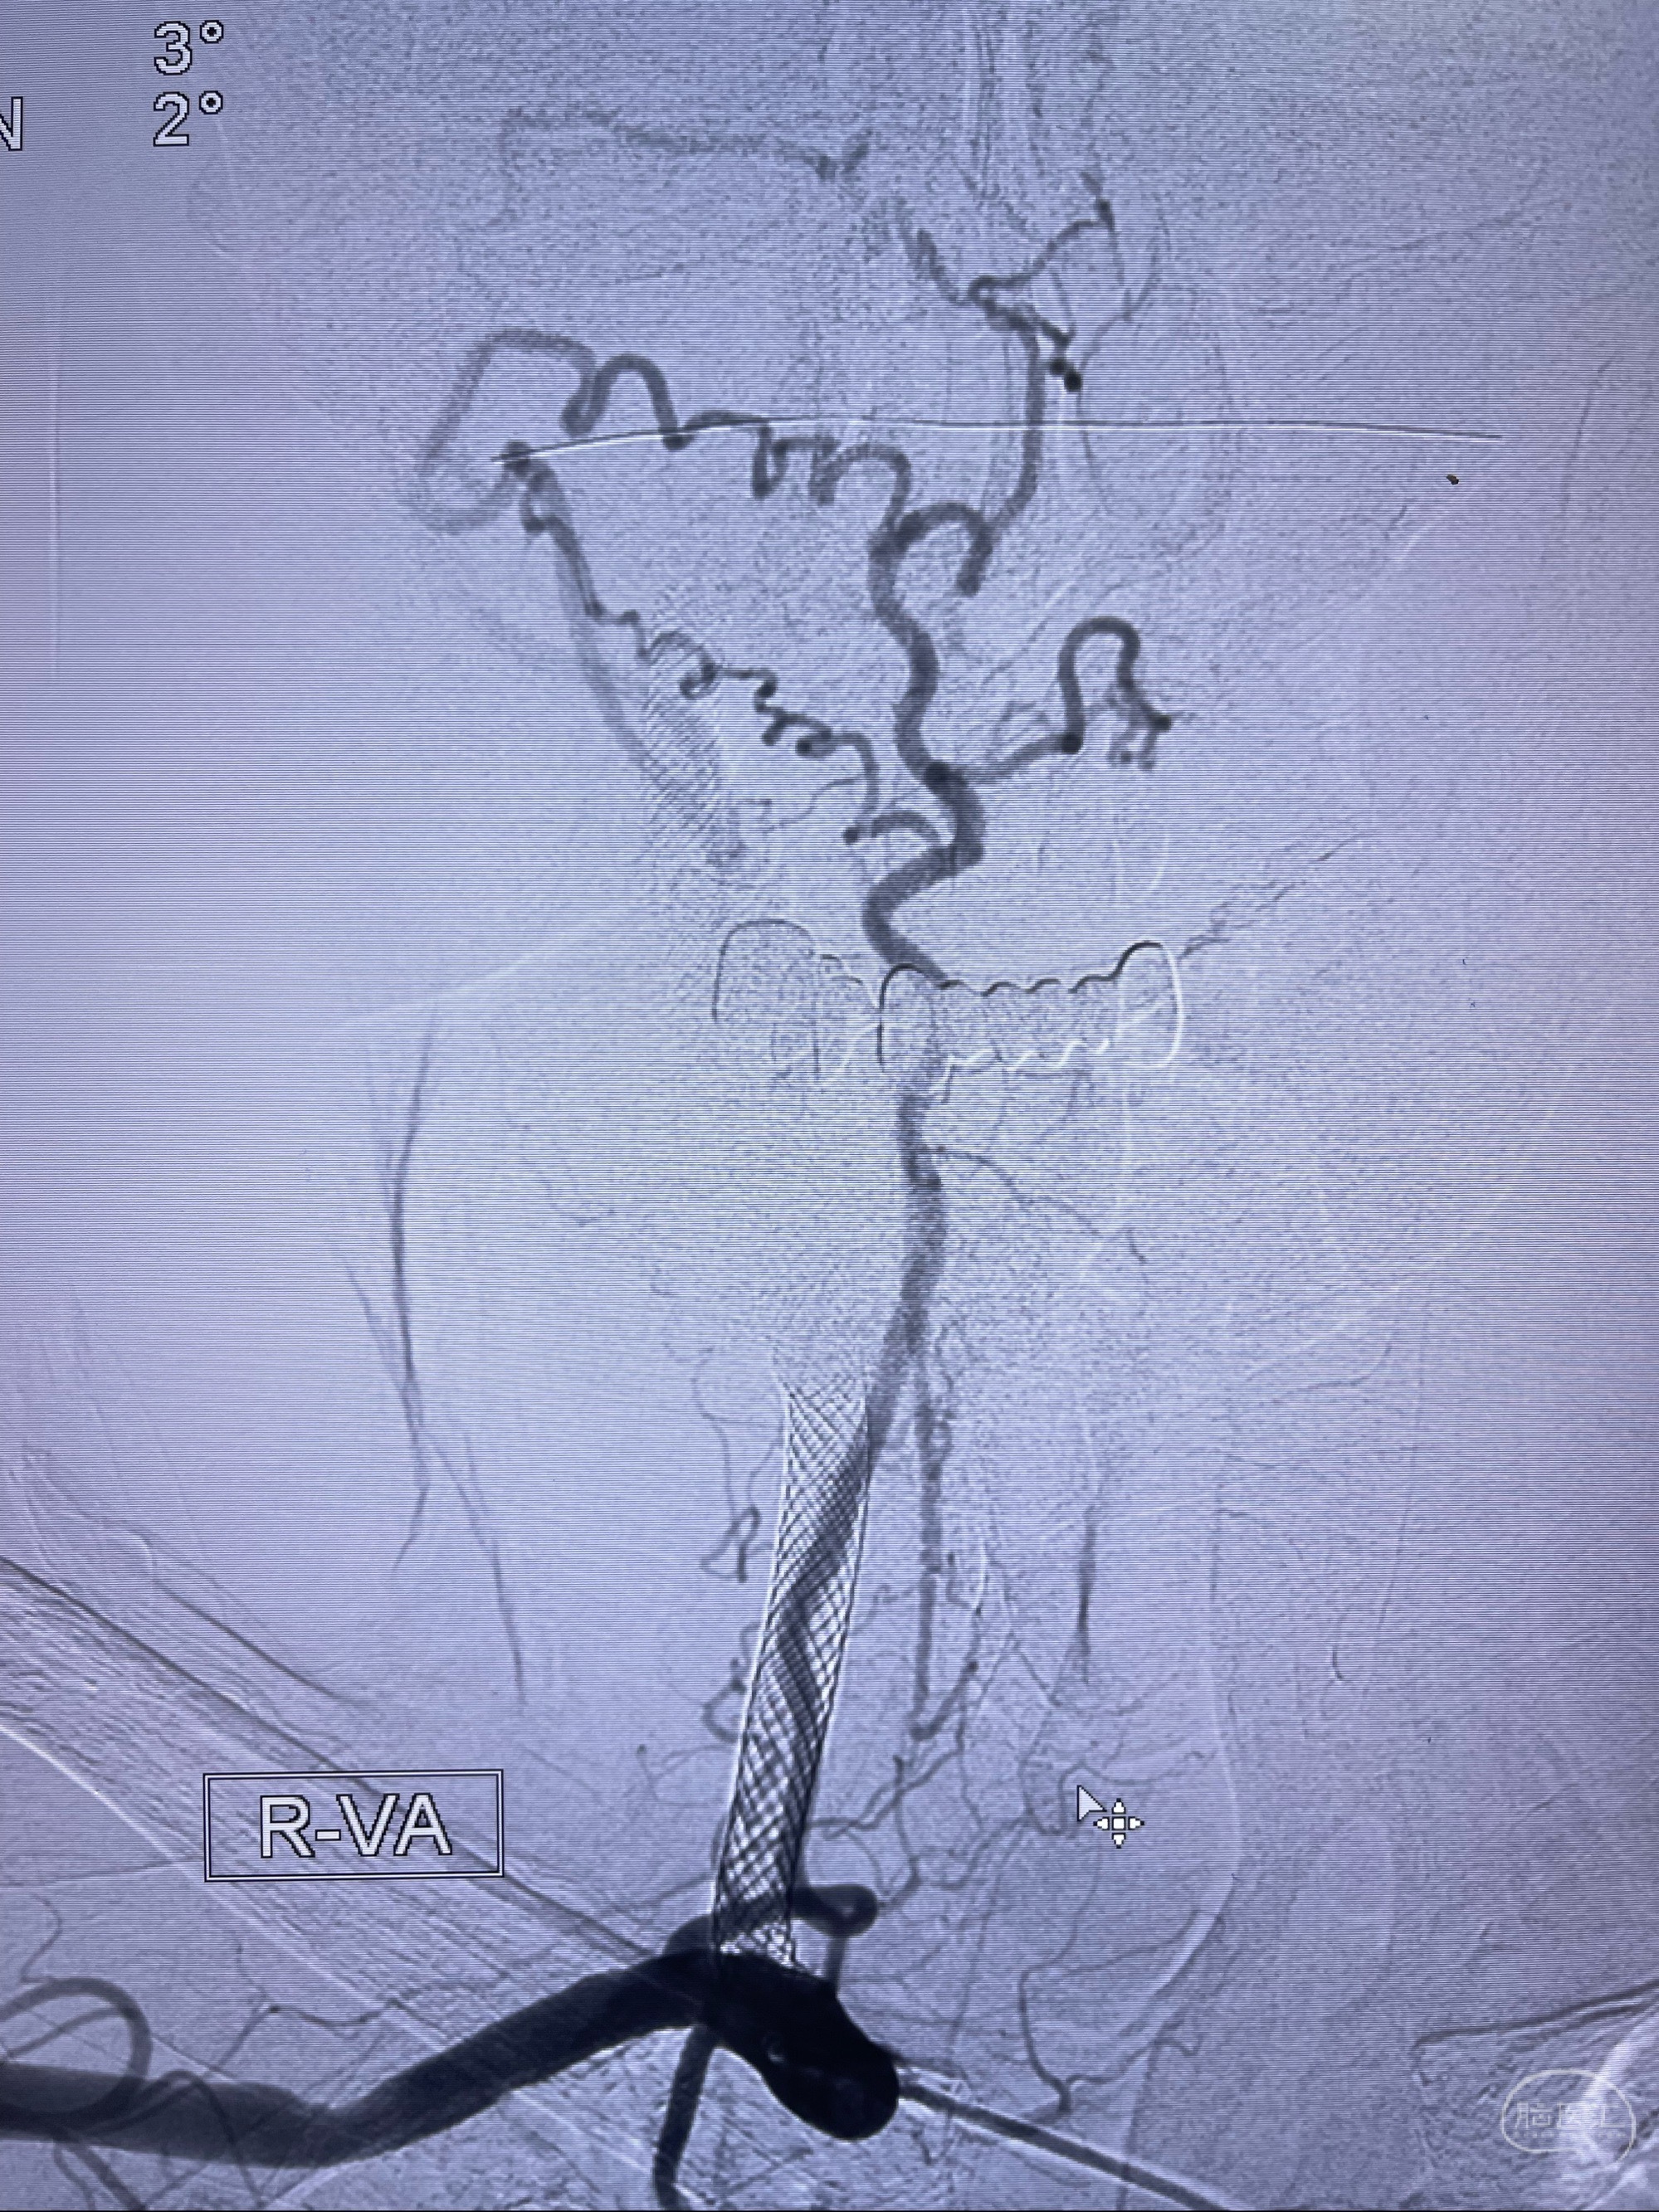

2023-07-10DSA:右侧颈内动脉岩骨段夹层伴中偏重度狭窄改变,左侧颈总动脉闭塞、右侧颈外动脉由右侧肋颈干甲颈干吻合代偿

箭头所示为颈内动脉岩骨段重度狭窄,结合MRI,考虑为肿瘤侵犯右侧颈内动脉

箭头以近至支架段管腔不规则狭窄

右侧椎动脉可见吻合代偿右侧颈外动脉

双抗准备后于2023-07-13在全麻下行右侧颈内动脉功能保护

088NeuroMAX100cm长鞘在125cmMPA及黑泥鳅导丝引导下超选择性插入右侧颈内动脉支架内

经导引导管造影显示支架远端颈内动脉不规则狭窄伴局部充盈缺损,同时行全身肝素化5ml